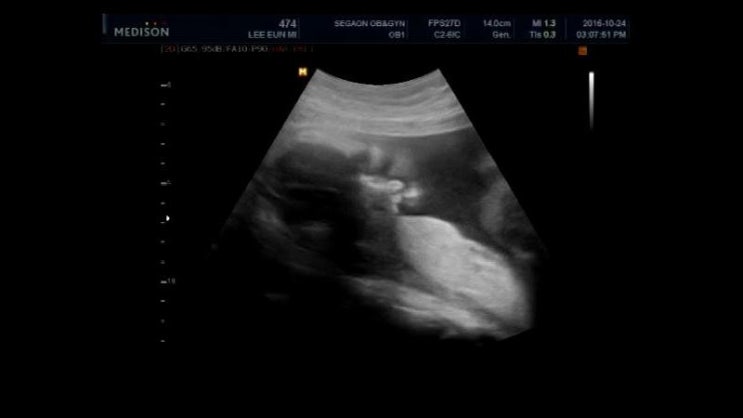

2016년 10월 24일 오복이 27주 3일차

4주만에 다시 만나 오복이~ 오늘은 임신성당뇨 검사하는날! 지난번 검진때 받아온 당뇨시액 ...